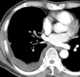

Large unilateral pleural effusion

A pleural effusion is accumulation of excessive fluid in the pleural space, the potential space that surrounds each lung. Under normal conditions, pleural fluid is secreted by the parietal pleural capillaries at a rate of 0.01 millilitre per kilogram weight per hour, and is cleared by lymphatic absorption leaving behind only 5–15 millilitres of fluid, which helps maintaining a functional vacuum between the parietal and visceral pleurae. [Source: Wikipedia ]